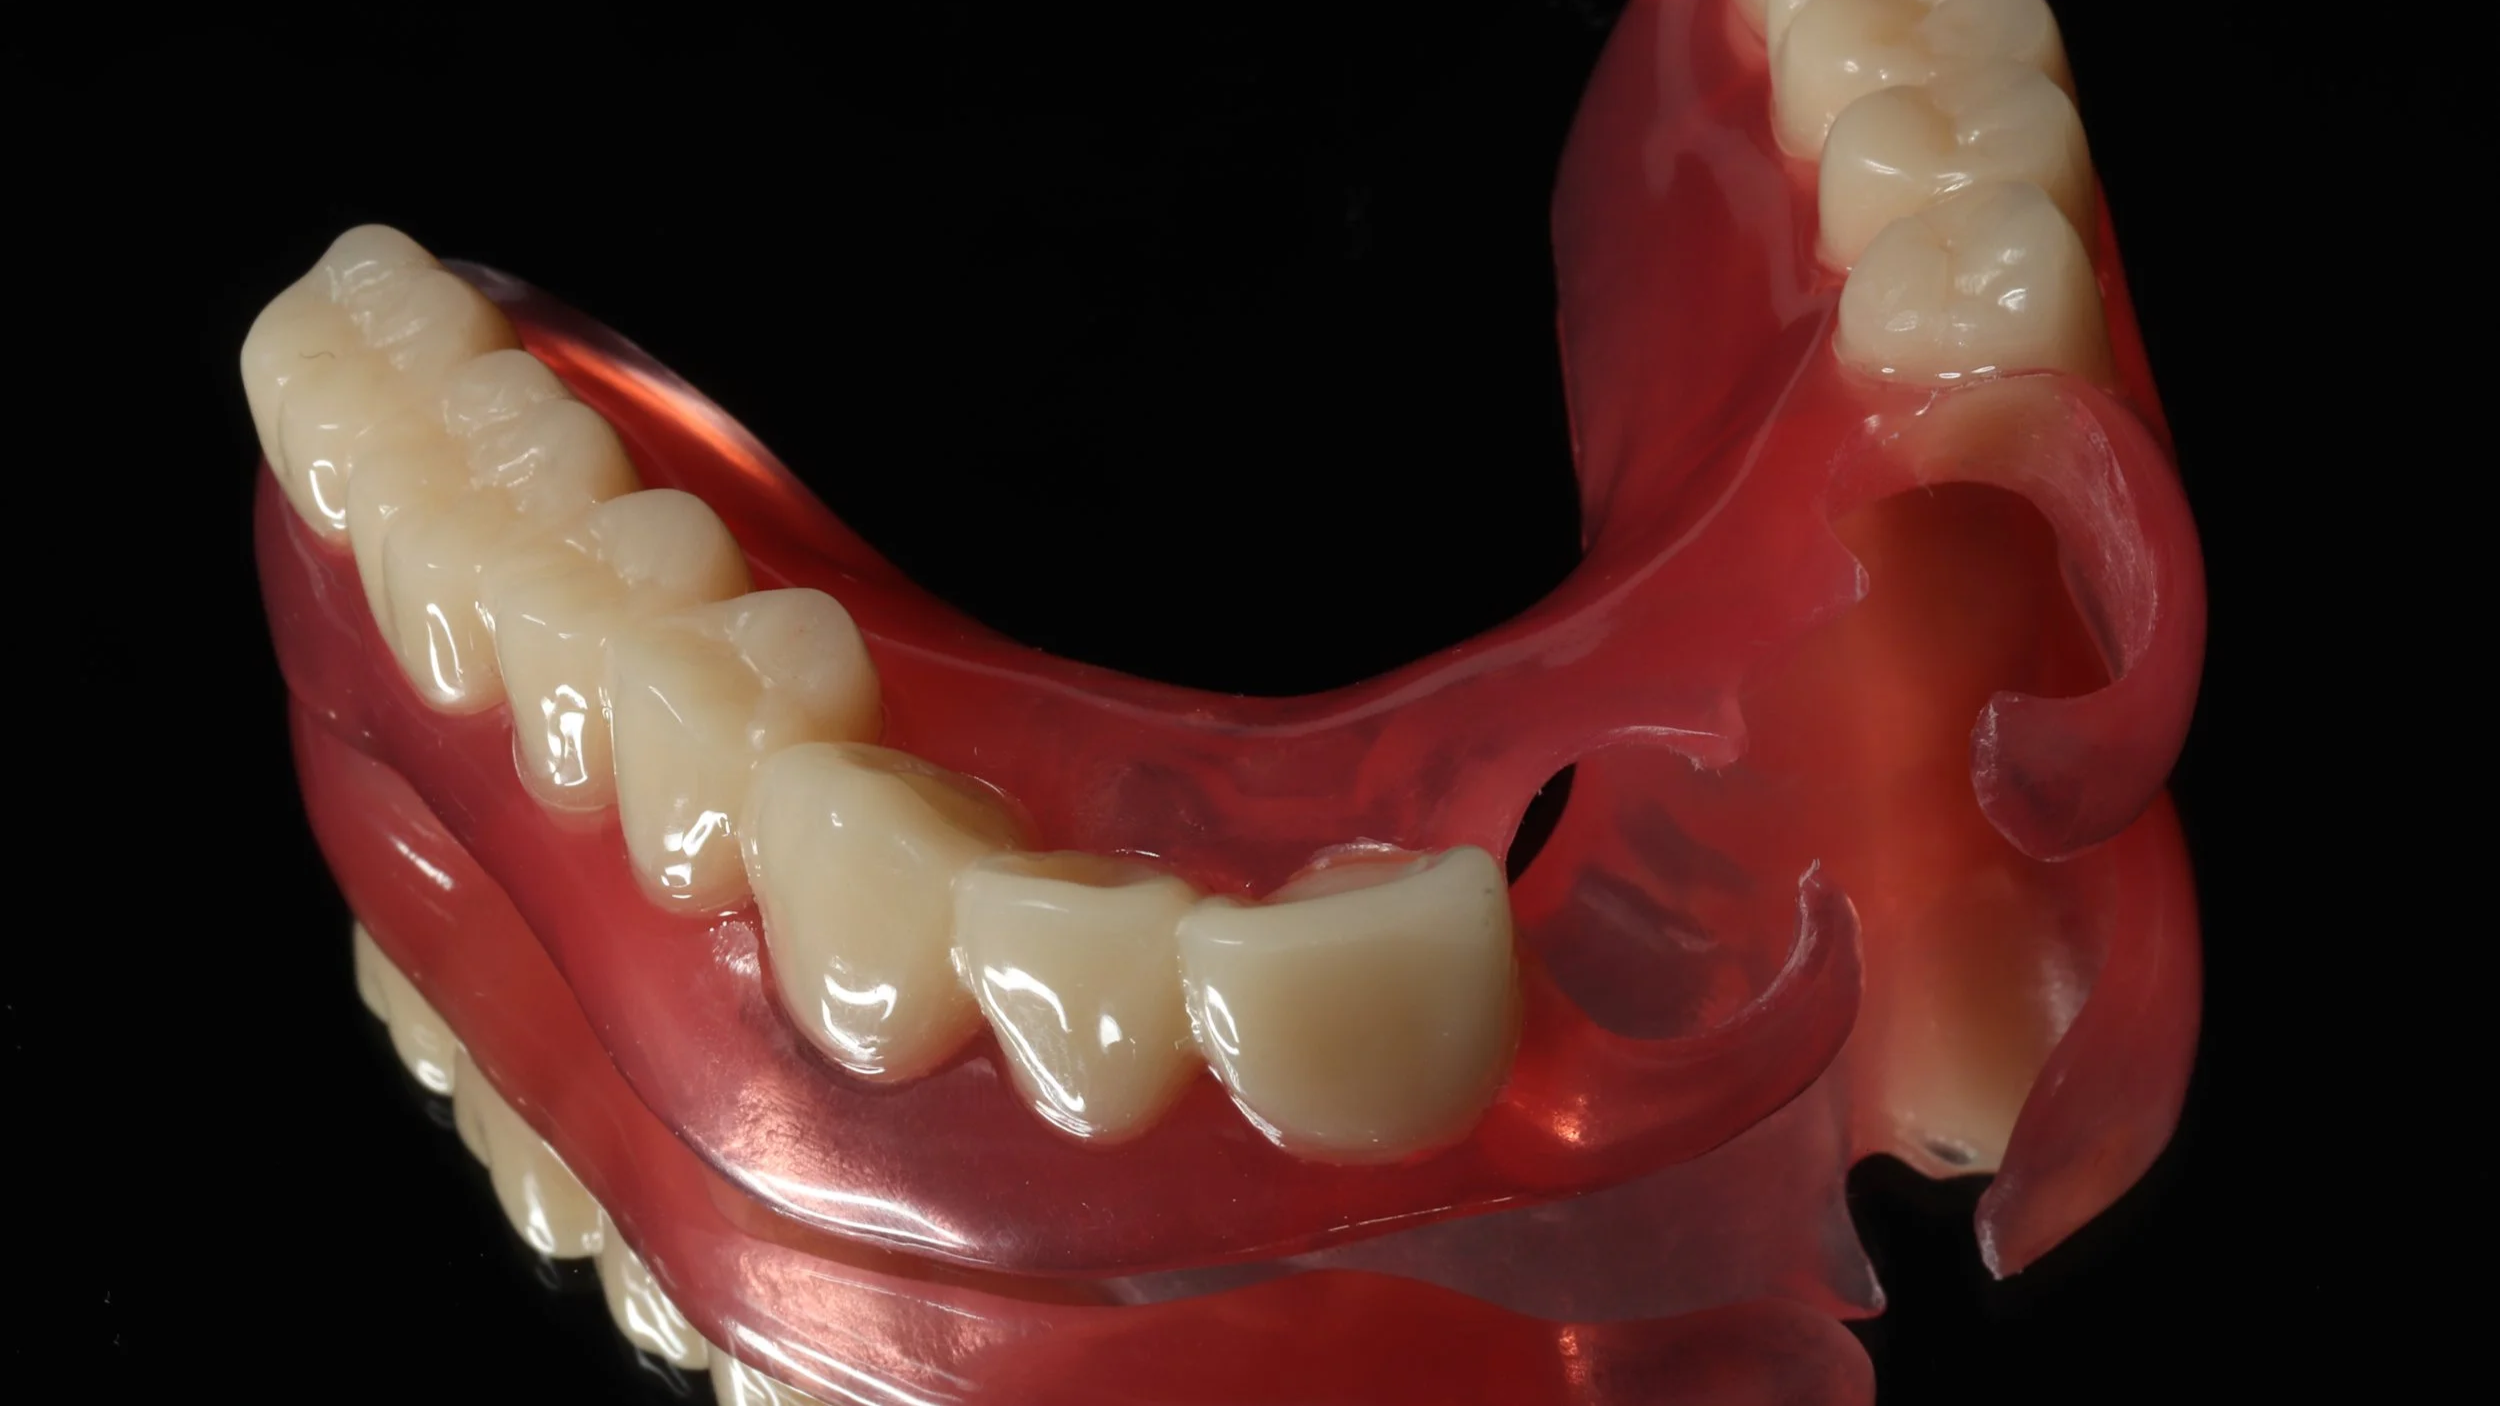

残せる歯は、しっかり根の治療を開始しつつ、新しい入れ歯を装着。内側を金属で薄く作る事で違和感の軽減を図りました。

デジタルデンチャー

内側を金属で薄く作る事で違和感の軽減を図りました。前歯の見える部分は、透明の素材を使用。口の状態によってピンク色のときもあります。